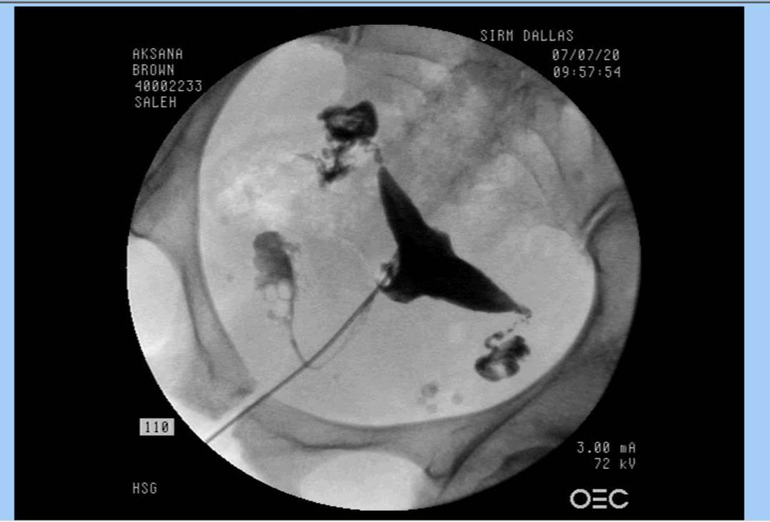

На ГСГ врач сказал что обе трубы непроходимы. Кто разбирается в снимках, как считаете, так ли это? Мне кажется слева реагент все-таки вытек.

Да, черным - это полость матки и ячники. Правая труба у меня вопросов вообще не вызывает, она вся в пунктирах. То есть проходит еле-еле.

А вот левая - у меня под вопросом. Врач сказал, что трубы непроходимы обе - одна на 90%, другая - на 95%.

Контраст же протек, если ворсинки работают, то и як пройдет. Мне так кажется. Это не безнадежный снимок.